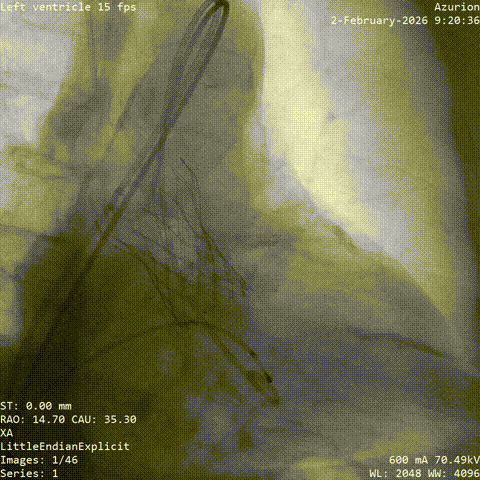

冠脉治疗后一周,张老先生整体状态平稳,进入主动脉瓣置换阶段。团队从股动脉建立通道,将人工瓣膜送至主动脉瓣位置。结合术前评估结果和术中情况,这次手术未进行球囊预扩张,而是直接完成瓣膜释放。

术中,因患者主动脉弓形态较复杂,器械通过一度受阻。团队根据术中情况及时调整策略,最终顺利完成过弓、跨瓣和瓣膜释放。造影及经胸超声显示,瓣膜位置理想、功能良好,左右冠脉血流通畅,未见瓣周漏及血管并发症。

▲根部造影

▲血管扭曲预塑形导丝支撑不足

▲更换导丝后过弓过瓣

▲初始定位

▲左右重合位评估

▲左冠切线位评估

▲最终瓣膜造影

▲入路检查